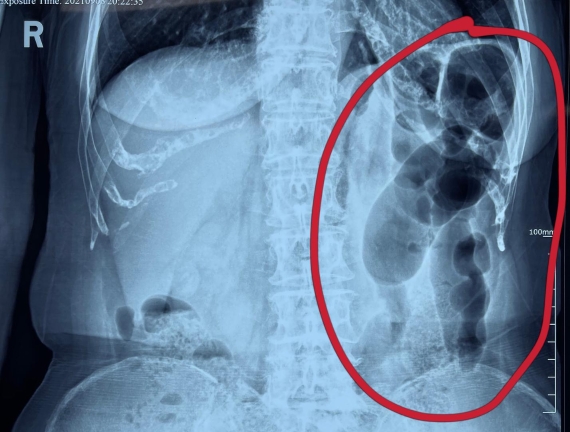

據(jù)省醫(yī)院消化病院消化二科姜子曄醫(yī)生介紹,韓大娘今年已經(jīng)73歲,家住哈爾濱市,一周前開始腹脹腹痛,有較為明顯的左側腹部疼痛,疼痛劇烈時會出現(xiàn)左側腹部鼓包情況,排氣排便后有所好轉。韓大娘家人見狀將其送到了黑龍江省醫(yī)院,門診檢查腹部平片提示為左側腹部積氣,口服全消化動力藥及通便治療后腹痛腹脹有所緩解,入院前再次突發(fā)左側腹痛加重伴有明顯腹脹,急診隨后以“腹痛腹脹原因待查”將韓大娘收入到消化病院消化二科。

姜子曄醫(yī)生熱情接待了韓大娘,為其進行了仔細查體,除了左側腹部壓痛并未見明顯異常,對癥給予灌腸后,韓大娘的腹脹有所緩解,第二天姜子曄醫(yī)生為韓女士進行了胃腸鏡檢查,也未見明顯異常。但此時韓大娘腹部平片結腸腸管擴張仍然很嚴重,腹痛腹痛也沒緩解,到底什么原因呢?消化二科主任陸以霞在查房時建議繼續(xù)給予韓大娘口服全消化動力藥,必要時灌腸治療,同時陸以霞主任在追問病史查體時發(fā)現(xiàn)韓大娘左下腹紅色皮疹和小水泡,反復抓撓腹部皮膚部分已結痂,高度懷疑為帶狀皰疹。